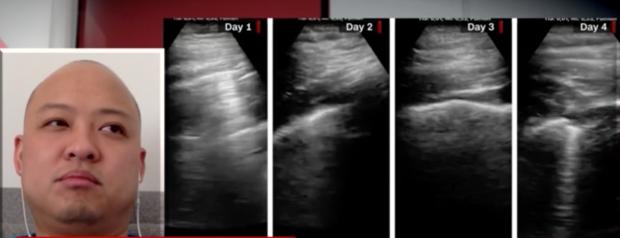

”Ziua 1 după ce am fost diagnosticat cu COVID-19. Durere în gât, durere de cap puternică, tuse seacă, dar fără dificultate respiratorie. Fără anormalități la plămâni, la ecografie”, a scris el, în primul astfel de mesaj.

”Ziua 2 după ce am fost diagnosticat cu COVID-19. Durere mai slabă în gât, tuse și durere de cap, fără dificultăți respiratorii sau durere în piept”. Însă, medicul a precizat că a început să observe schimbări în plămânii săi, precum linia pleurală îngroșată.

”A început diareea, tusea a început să mă lase. Aceleași modificări la plămâni”, a mai scris el, în a 3-a zi.

”Ziua 4 după diagnosticul de coronavirus. Mai multă tuse și foarte multă oboseală. Fără dispnee sau durere în piept”, a mai scris el, arătând alte modificări mici la plămânii săi.